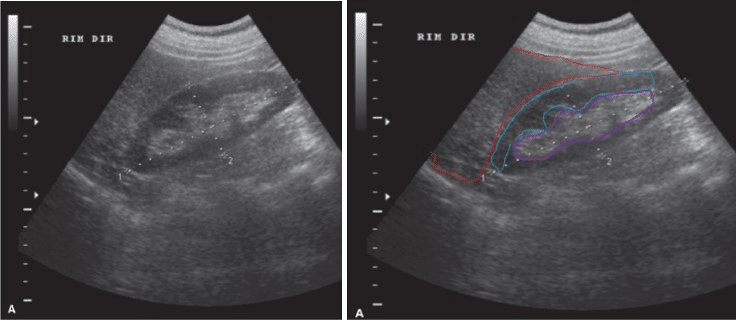

Dessa forma, na imagem abaixo é possível observar que a ultrassonografia do rim direito revela o córtex renal hipoecóico (destacado em azul), o seio renal hiperecogênico (marcado em roxo) e sua relação com o fígado (em vermelho).